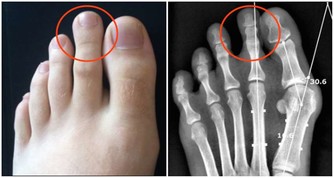

2、治療形成了凝塊的痔瘡

痔瘡會導致肛門周圍的血液產生凝結,附近的組織結痂。

如果你覺得自己出現了上述狀況,請即使就醫治療。